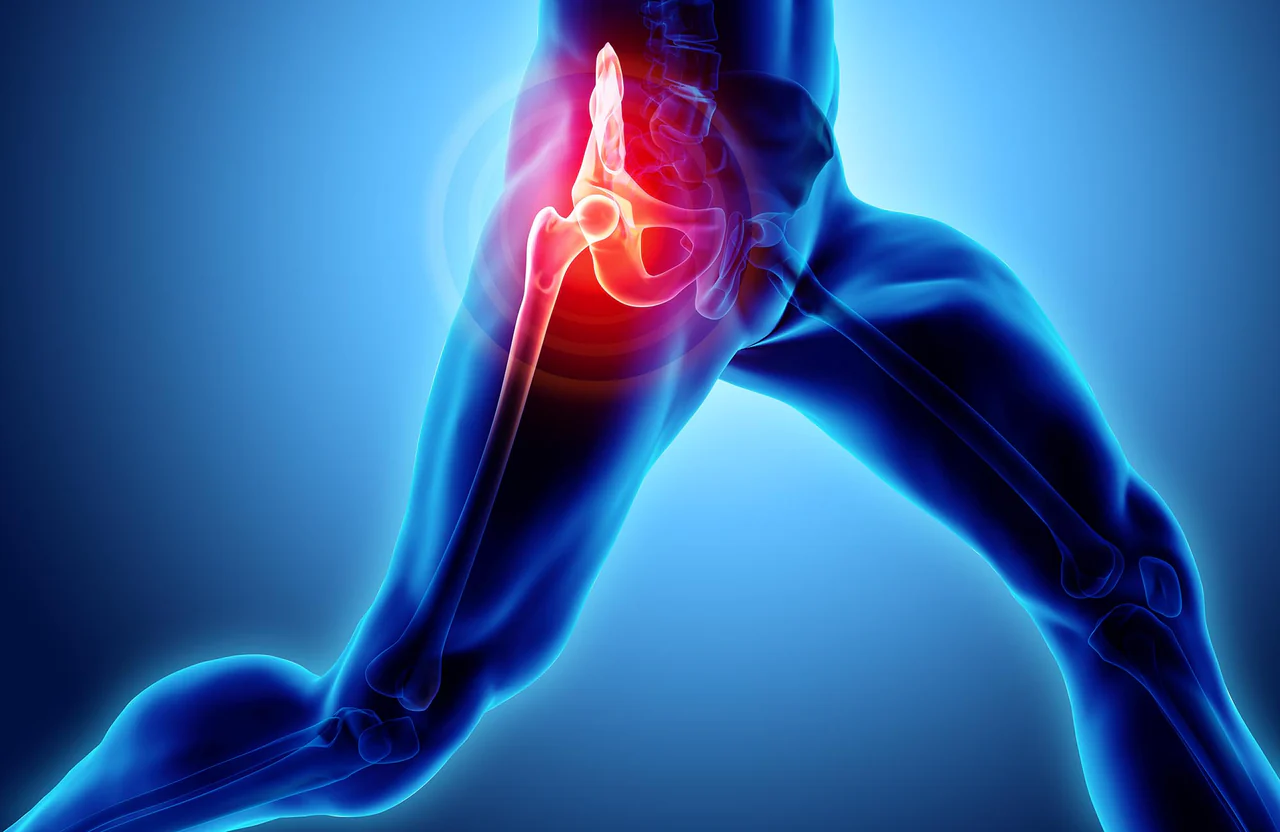

・運動後に股関節が痛むとはどういうことか

→ 痛みの感じ方・痛みが出る一般的なタイミング

→ 重だるい痛み〜鋭い痛みまでの違い

・運動後に股関節が痛むとはどういうことか

実際、こう感じて検索する方はとても多いです。運動後の股関節の痛みは、使った筋肉や関節まわりに負荷がかかったサインとして出ることがあると言われています。

痛みの出方は人それぞれで、「なんとなく重だるい感じが続く」「歩くとズキッとする」「脚を上げた瞬間に鋭い痛みが出る」など幅があります。タイミングもさまざまで、運動直後に違和感が出る人もいれば、翌日〜数日後に痛みを感じる人もいます。

「これって筋肉痛?」と思うケースも多いですが、股関節は体の中心に近く、複数の筋肉や関節が関わるため、太もも・お尻・鼠径部(足の付け根)など、痛む場所が少しわかりづらいのも特徴です。